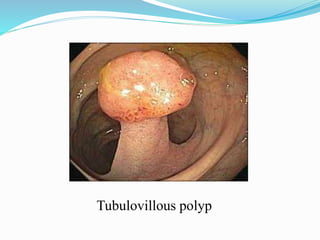

This document discusses colorectal polyps. It defines polyps and describes their types, including neoplastic and non-neoplastic polyps. It discusses adenomatous polyps in depth, noting their malignant potential increases with size over 1cm and villous architecture. Radiological diagnostic methods for polyps including single and double contrast barium enema and CT colonography are explained. The document provides an overview of polyp pathogenesis and genetic syndromes like FAP that increase cancer risk.